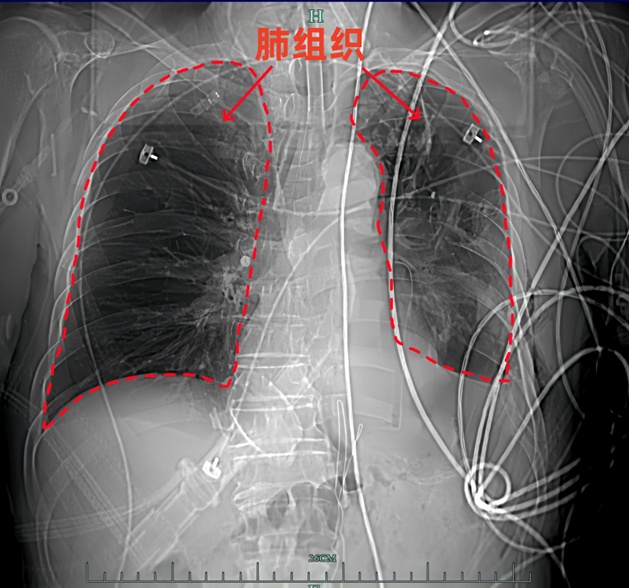

红色的右肺区域和黄色的左肺区域对比明显,左肺几乎消失,右肺的体积也有减小。

而胃和肠管挤占了肺的空间,肺就被越压越小,最后在CT影像上几乎看不见,就好像消失了一样。

对比上图可见,治疗后,不仅左肺“重新出现”,右肺的体积也得到了恢复。

结合季哥的病例,他提醒,由于膈肌的位置特殊,毗邻心脏和肺,一旦破损,其危害是多方面的:肺组织受压迫后,会导致肺体积缩小、肺血管异常,严重影响呼吸功能还会诱发肺实变、纤维化等病变。